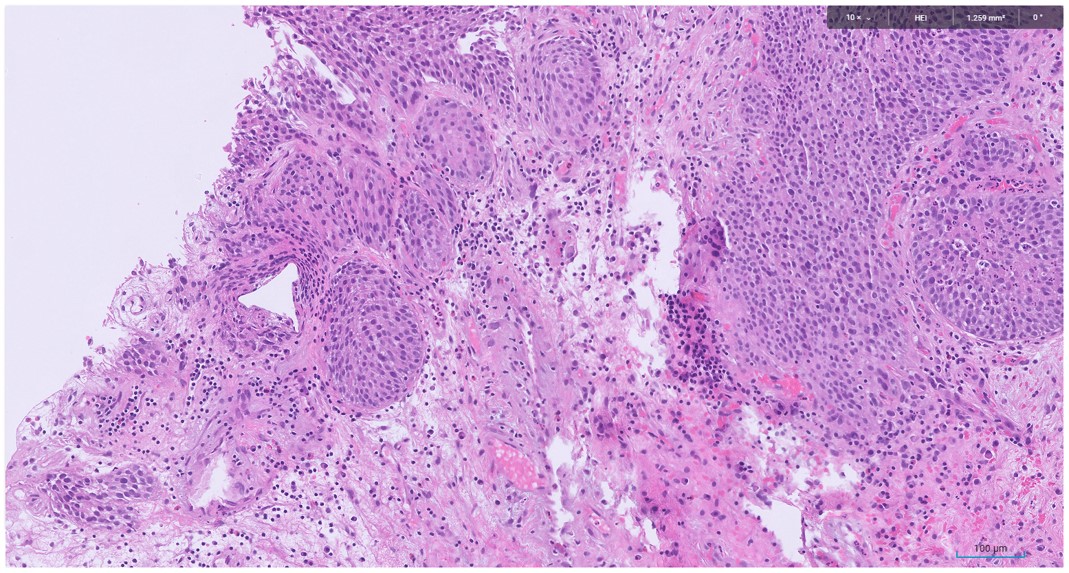

Microscopic image possibly detecting cancerous areas in human tissue